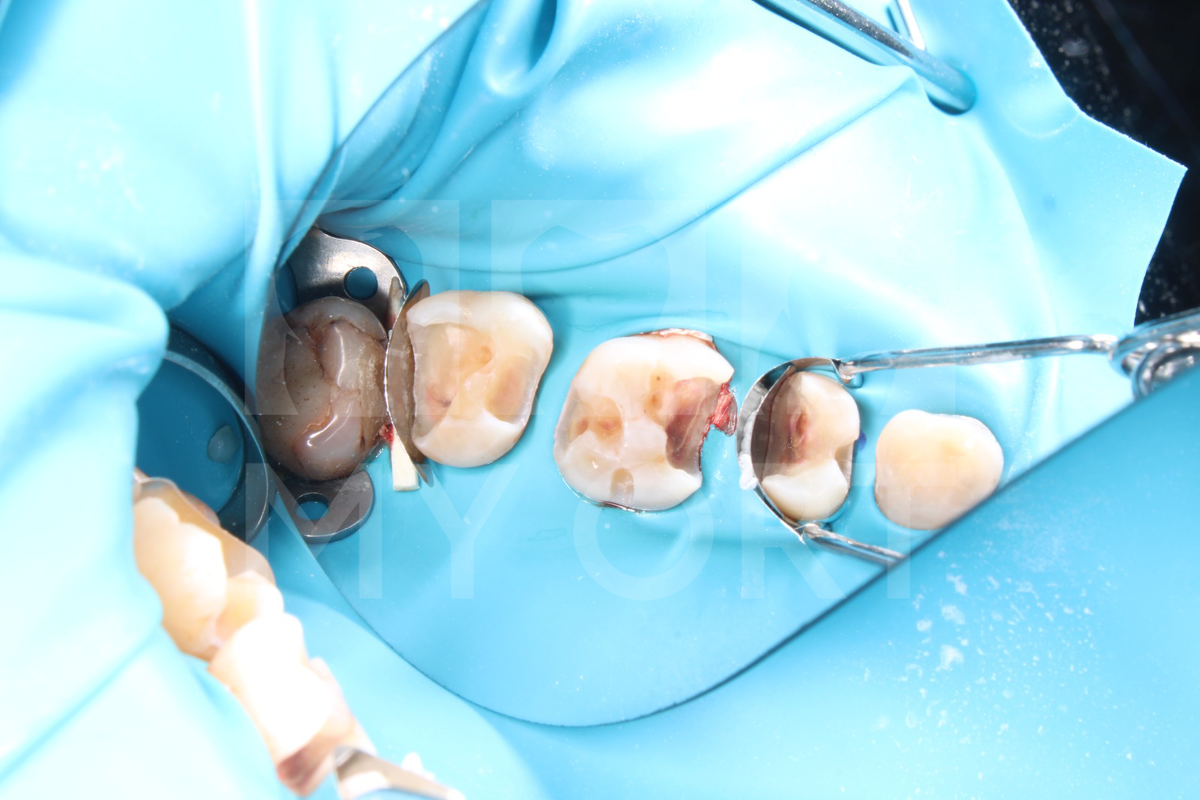

Первым делом я сделала анестезию и поставила изоляцию оптрагейт. Кстати, самое сложное в этом клиническом случае было то, что зубы находились на расстоянии друг от друга. Провела черновое препарирование: были удалены старые пломбы и кариозные ткани. А также был установлен коффердам, для изоляции зубов и предотвращения инфицирования.

На втором этапе я столкнулась с отсутствием соседних опорных структур, но смогла восстановить зубы. Я обработала и запломбировала полости, несмотря на сложные условия работы. Провела шлифование и полировку реставраций чашечками, щеточками и резиночками.

В одном зубе я вскрыла пульпу, к счастью, симптомов воспаления там не наблюдалось, поэтому канал был просто запломбирован.Так же я использовала тефлон для дополнительной защиты при работе с десной.